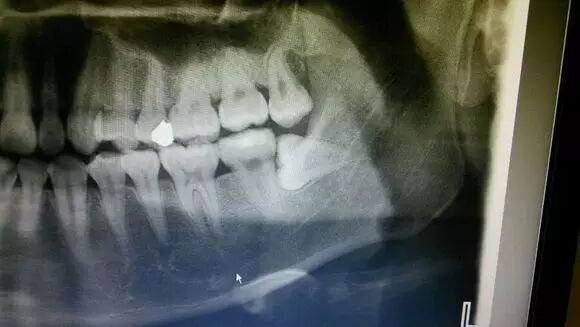

荷兰一项研究显示, 对于7项影像学预测指标,曲面体层片的附加值 过低而无法在术前用来排除下颌第三磨牙(MM3)拔除术后下牙槽神经(IAN)损伤可能性。 对于神经管改道、神经管白线中断及根部暗影这几项指标,曲面体层片的附加值可以考虑用来在术前排除MM3拔除术后 IAN损伤可能性。论文2016年12月15日在线发 表于《口腔颌面外科学杂志 》(J Oral Maxillofac Surg)。

研究者通过检索 MEDLINE和EMBASE, 筛选有关曲面体层片7项预测指标对MM3拔除术后IAN损伤诊断准确性的研究, 这7项指标包括: 牙根相关指征(根部暗影、根偏曲、根狭窄、根尖暗区及劈裂)和神经管相关指征(神经管白线的中断,神经管改道及狭窄)。 结果共纳入8篇符合标准的研究进行荟萃分析。7项指标总敏感度和特异性范围分别为0.06~ 0.49及0.81~0.97。受试者-操作者曲线下方总面积范围为0.42~0.89。总的阳性预测值和阴性预测值范围分别为7.5%~ 26.6%及95.9%~97.7%。 确定IAN损伤阳性症状的附加值(阳性预测值减去先验概率)范围为3.4%~ 22.2%。排除IAN损伤阴性症状的附加值(1减去先验概率)范围为0.1%~ 2.2%。(张翼飞 编译)